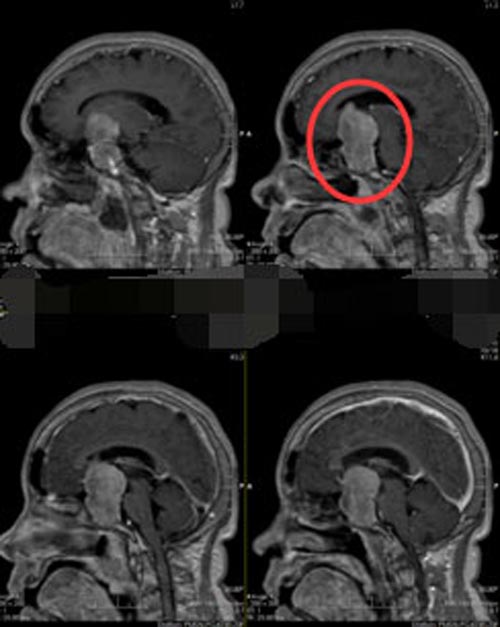

意识到问题的严重性后,家人经过多方打听来到广东三九脑科医院神经外五科。医生给蔡阿姨做了更加全面的检查,头颅MR示:鞍区垂体大腺瘤,病变向上突入左侧脑室前角,激素八项提示:生长激素及垂体泌乳素增高。神经外五科的治疗团队讨论后一致认为,垂体腺瘤诊断明确,MRI提示T1低密度等信号影,T2高密度等信号影,右侧有囊性病变,有明显的内分泌症状。

▲手术前